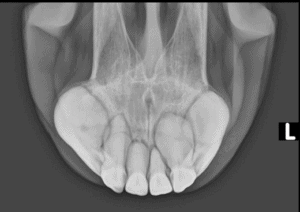

Bei der jĂ€hrlichen Zahnkontrolle von dieser 24-jĂ€hrige Stute fiel bei der Untersuchung dieses Jahr eine VerĂ€nderung der SchneidezĂ€hne auf. Das Zahnfleisch ist aufgetrieben, es befindet sich ĂŒbermĂ€ssigem Zahnstein auf die ZĂ€hnen und auf der rechte Oberkiefer (links im Bild, umkreist) sieht man eine knollige Auftreibung vom Ă€usseren SchneidezĂ€hne. Einzelne ZĂ€hne im Oberkiefer waren zudem etwas locker. Um zu sehen, wie weit die Erkrankung bereits fortgeschritten ist, wurden Röntgenbilder von den SchneidezĂ€hnen im Ober- sowie Unterkiefer gemacht. Dort sah man, dass die ZĂ€hnen auch unter dem Zahnfleisch verĂ€ndert sind, und diese knollige Verformung sich nicht nur auf den einen Zahn begrenzt.

Es steht fĂŒr Equine Odontoclastic Tooth Resorption and Hypercementosis. Das bedeutet, der Zahn löst sich auf (Resorption) und gleichzeitig bildet sich Zement im ĂŒbermĂ€ssigem Mass (Hyperzementose). Das Resultat ist diese knollig-aussehende ZĂ€hne die man bei dieser Stute gefunden hatte. Die klinische Zeichen einer EORTH sind aufgetriebenes Zahnfleisch, Zahnstein im Bereich der SchneidezĂ€hnen, entzĂŒndetes Zahnfleisch, mit oder ohne kleine roten BlĂ€schen (Parodontose) und eine Lockerung der SchneidezĂ€hnen. EOTRH tretet meist bei Ă€lteren Pferden, ab 15 Jahren, auf und ist eine sehr schmerzhafte Erkrankung.